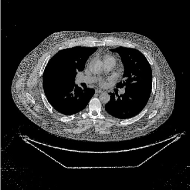

This paper was inspired by a simple observation related to our recent study [34]: for the penalized weighted-least squares (PWLS) reconstruction method using prior with a learned ST (PWLS-ST-) [34], the sparsification error histograms match a Laplace distribution over the iterations; see Fig. 1. The question then arises, “Does the learned prior experience model mismatch in testing stage?” To answer this question, we aim to investigate learned STs for regularization. This paper

The term denotes a -based sparsification error [3, 4, 5]. We expect to be more robust to sparsity model mismatch than the -based sparsification error used in [34, 36]. Fig. 1 shows histograms of sparsification error at different outer iterations of the PWLS-ST- method. Over the iterations, the sparsification error histograms appear more like a Laplace distribution than a Gaussian distribution. This observation suggests that the proposed prior model is more suitable than the prior model for PWLS-ST-based reconstruction. Section III-B1 shows that the proposed -based sparsification error term, , improves the accuracy of reconstruction compared to the prior model in [34, 36].

| views | ||||

| (a) , | (b) , | (c) , | (d) , |